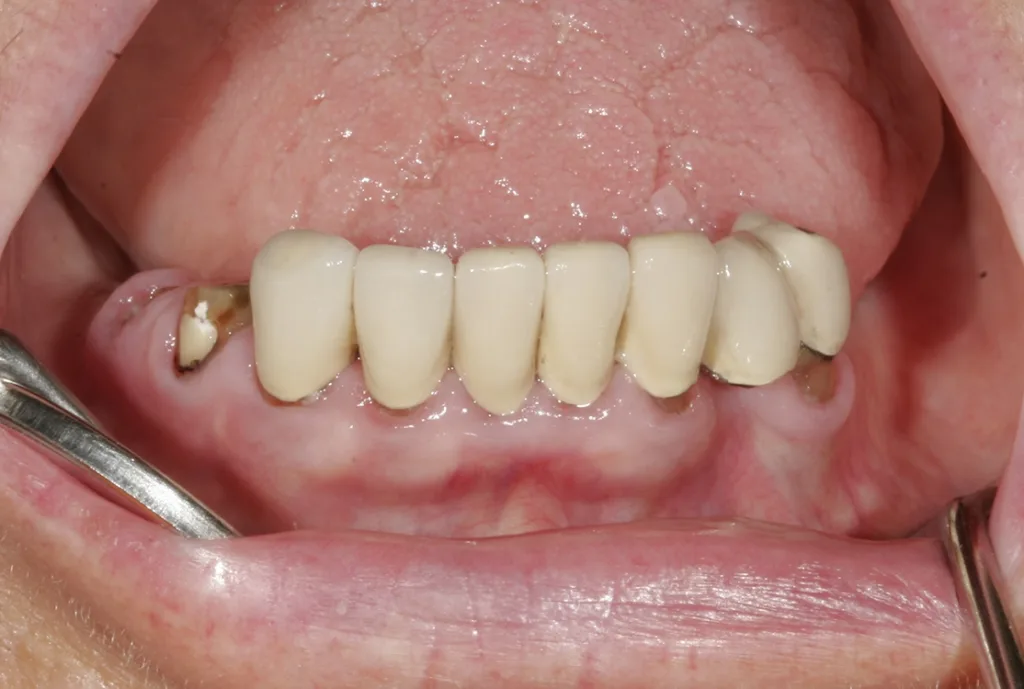

Eine noch verhältnismäßig jung wirkende 76-jährige Patientin musste im Unterkiefer neu versorgt werden, da die alte VMK-Brückenkonstruktion wegen Pfeilerverlusts komplett entfernt werden sollte. Seit mehr als 10 Jahren bestand bereits eine Teleskopversorgung im Oberkiefer – nunmehr war auch für den Unterkiefer eine solche vorgesehen. Ein besonderes Anliegen war der Patientin eine brückenartige Konstruktion, d.h. ohne Sublingualbügel. Bei der Farbgestaltung war der Wunsch, dass sie eine Nuance heller sein sollte als die Zähne im Oberkiefer, und keinesfalls sollten die Zähne einen gelblichen Stich bekommen. Beim Situationsmodell von bukkal zeigte sich, dass schon früher der Zahn 33 unter der Brücke entfernt worden war (Abb. 1) und der Knochen in diesem Bereich stark atrophiert war. In der Ansicht von lingual (Abb. 2) sind der „Zahnstummel“ 44 und die Extraktionswunde 45 gut ersichtlich.

Beim ersten Patientenkontakt zeigte sich eine aufgrund der Situation sehr angespannte, unzufriedene Patientin; ein Lächeln war praktisch nicht möglich (Abb. 3). Obgleich die Oberkiefer-Teleskopversorgung (Abb. 4) im Zahnhalsbereich kosmetisch nicht mehr sehr schön war, fiel dies aufgrund der stark deckenden Oberlippe in situ nicht auf. Funktionell war die Versorgung nach wie vor ohne jegliche Beanstandung, was sehr für den damaligen Techniker ebenso wie auch für die Teleskoptechnik selbst spricht. Die alte VMK-Brücke im Unterkiefer (Abb. 5) war ästhetisch noch immer in einem guten Zustand. Bei genauerer Betrachtung wurde die grazile Ausführung ersichtlich; bei 31 und 32 mesial schimmerte der Opaker im Halsbereich leicht durch, was darauf schließen ließ, dass das Platzangebot hier nicht übermäßig groß war. Aufgrund der Grazilität der Zähne kann in diesem Bereich oft nicht viel nachpräpariert werden; entsprechend schwierig ist es, in solchen Fällen mit Doppelkronen ein ästhetisch befriedigendes Ergebnis zu realisieren.